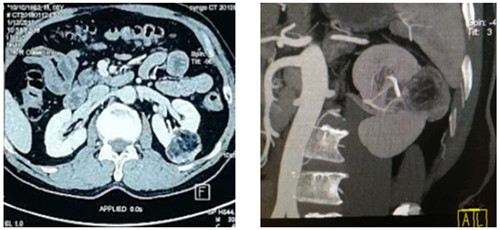

如圖一圖二為腫瘤位置及大小,圖三即為手術操作通道(5mm、10mm、12mm),術中游離出腎動脈后,用圖四的血管夾臨時阻斷腎臟血液供應,剜除腫瘤后,在腔鏡下縫合腎臟,確定縫合嚴密,再恢復腎臟血供!要求阻斷時間不能超過30分鐘,此例患者阻斷17分鐘!此類手術技術難度大,腹腔鏡下縫合要求高,并對血供阻斷有時間要求!